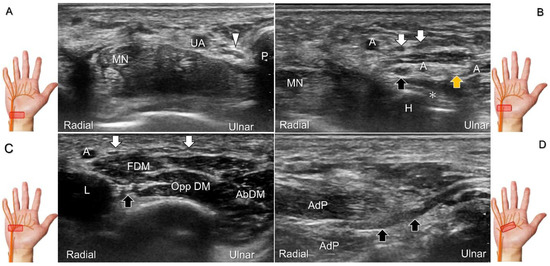

Scanning Technique

The transducer is placed on the mid-palm in the axial plane (Figure 28A). The palmar common digital nerves course beside the flexor digitorum profundus/superficialis tendons with the palmar common digital artery, and they are superficial to the palmar interosseous muscles (Figure 28B). Moving the transducer more distally, the palmar proper digital nerves can be identified alongside all phalanges (Figure 28C,D).

Figure 13. Sonographic imaging (short-axis view) shows the ulnar nerve within the Guyon’s canal (A), separation of branches beside the pisohamate hiatus (B), deep branch of the ulnar nerve located between the hypothenar muscles distal to the hook of the hamate (C). Long-axis view (through pivoting the transducer) shows the segment of the deep branch within the adductor pollicis muscle (D). Arrowhead: ulnar nerve; white arrows: superficial branch of the ulnar nerve; black arrows: deep branch of the ulnar nerve; orange arrow: branch of the ulnar nerve to the abductor digiti minimi; *: pisohamate ligment MN: median nerve; UA: ulnar artery; P: pisiform; H: hook of hamate; A: artery; L: lumbrical muscle; FDM: flexor digiti minimi brevis muscle; Opp DM: opponens digiti minimi muscle; AbDM: abductor digiti minimi muscle; AdP: adductor pollicis muscle.

Figure 28. Sonographic imaging of the palmar common digital nerves in short-axis (A) and long-axis (B) views. Palmar proper digital nerves from the base (C) to the head of the proximal phalanx (D). White arrowheads: palmar common digital nerves; black arrowheads: palmar proper digital nerves. T: flexor tendon; L: lumbricalis muscle; PIO: palmar interosseous muscle; FDS: flexor digitorum superficialis tendon; FDP: flexor digitorum profundus tendon; A: artery; VP: volar plate; PP: proximal phalanx; PPh: head of the proximal phalanx.